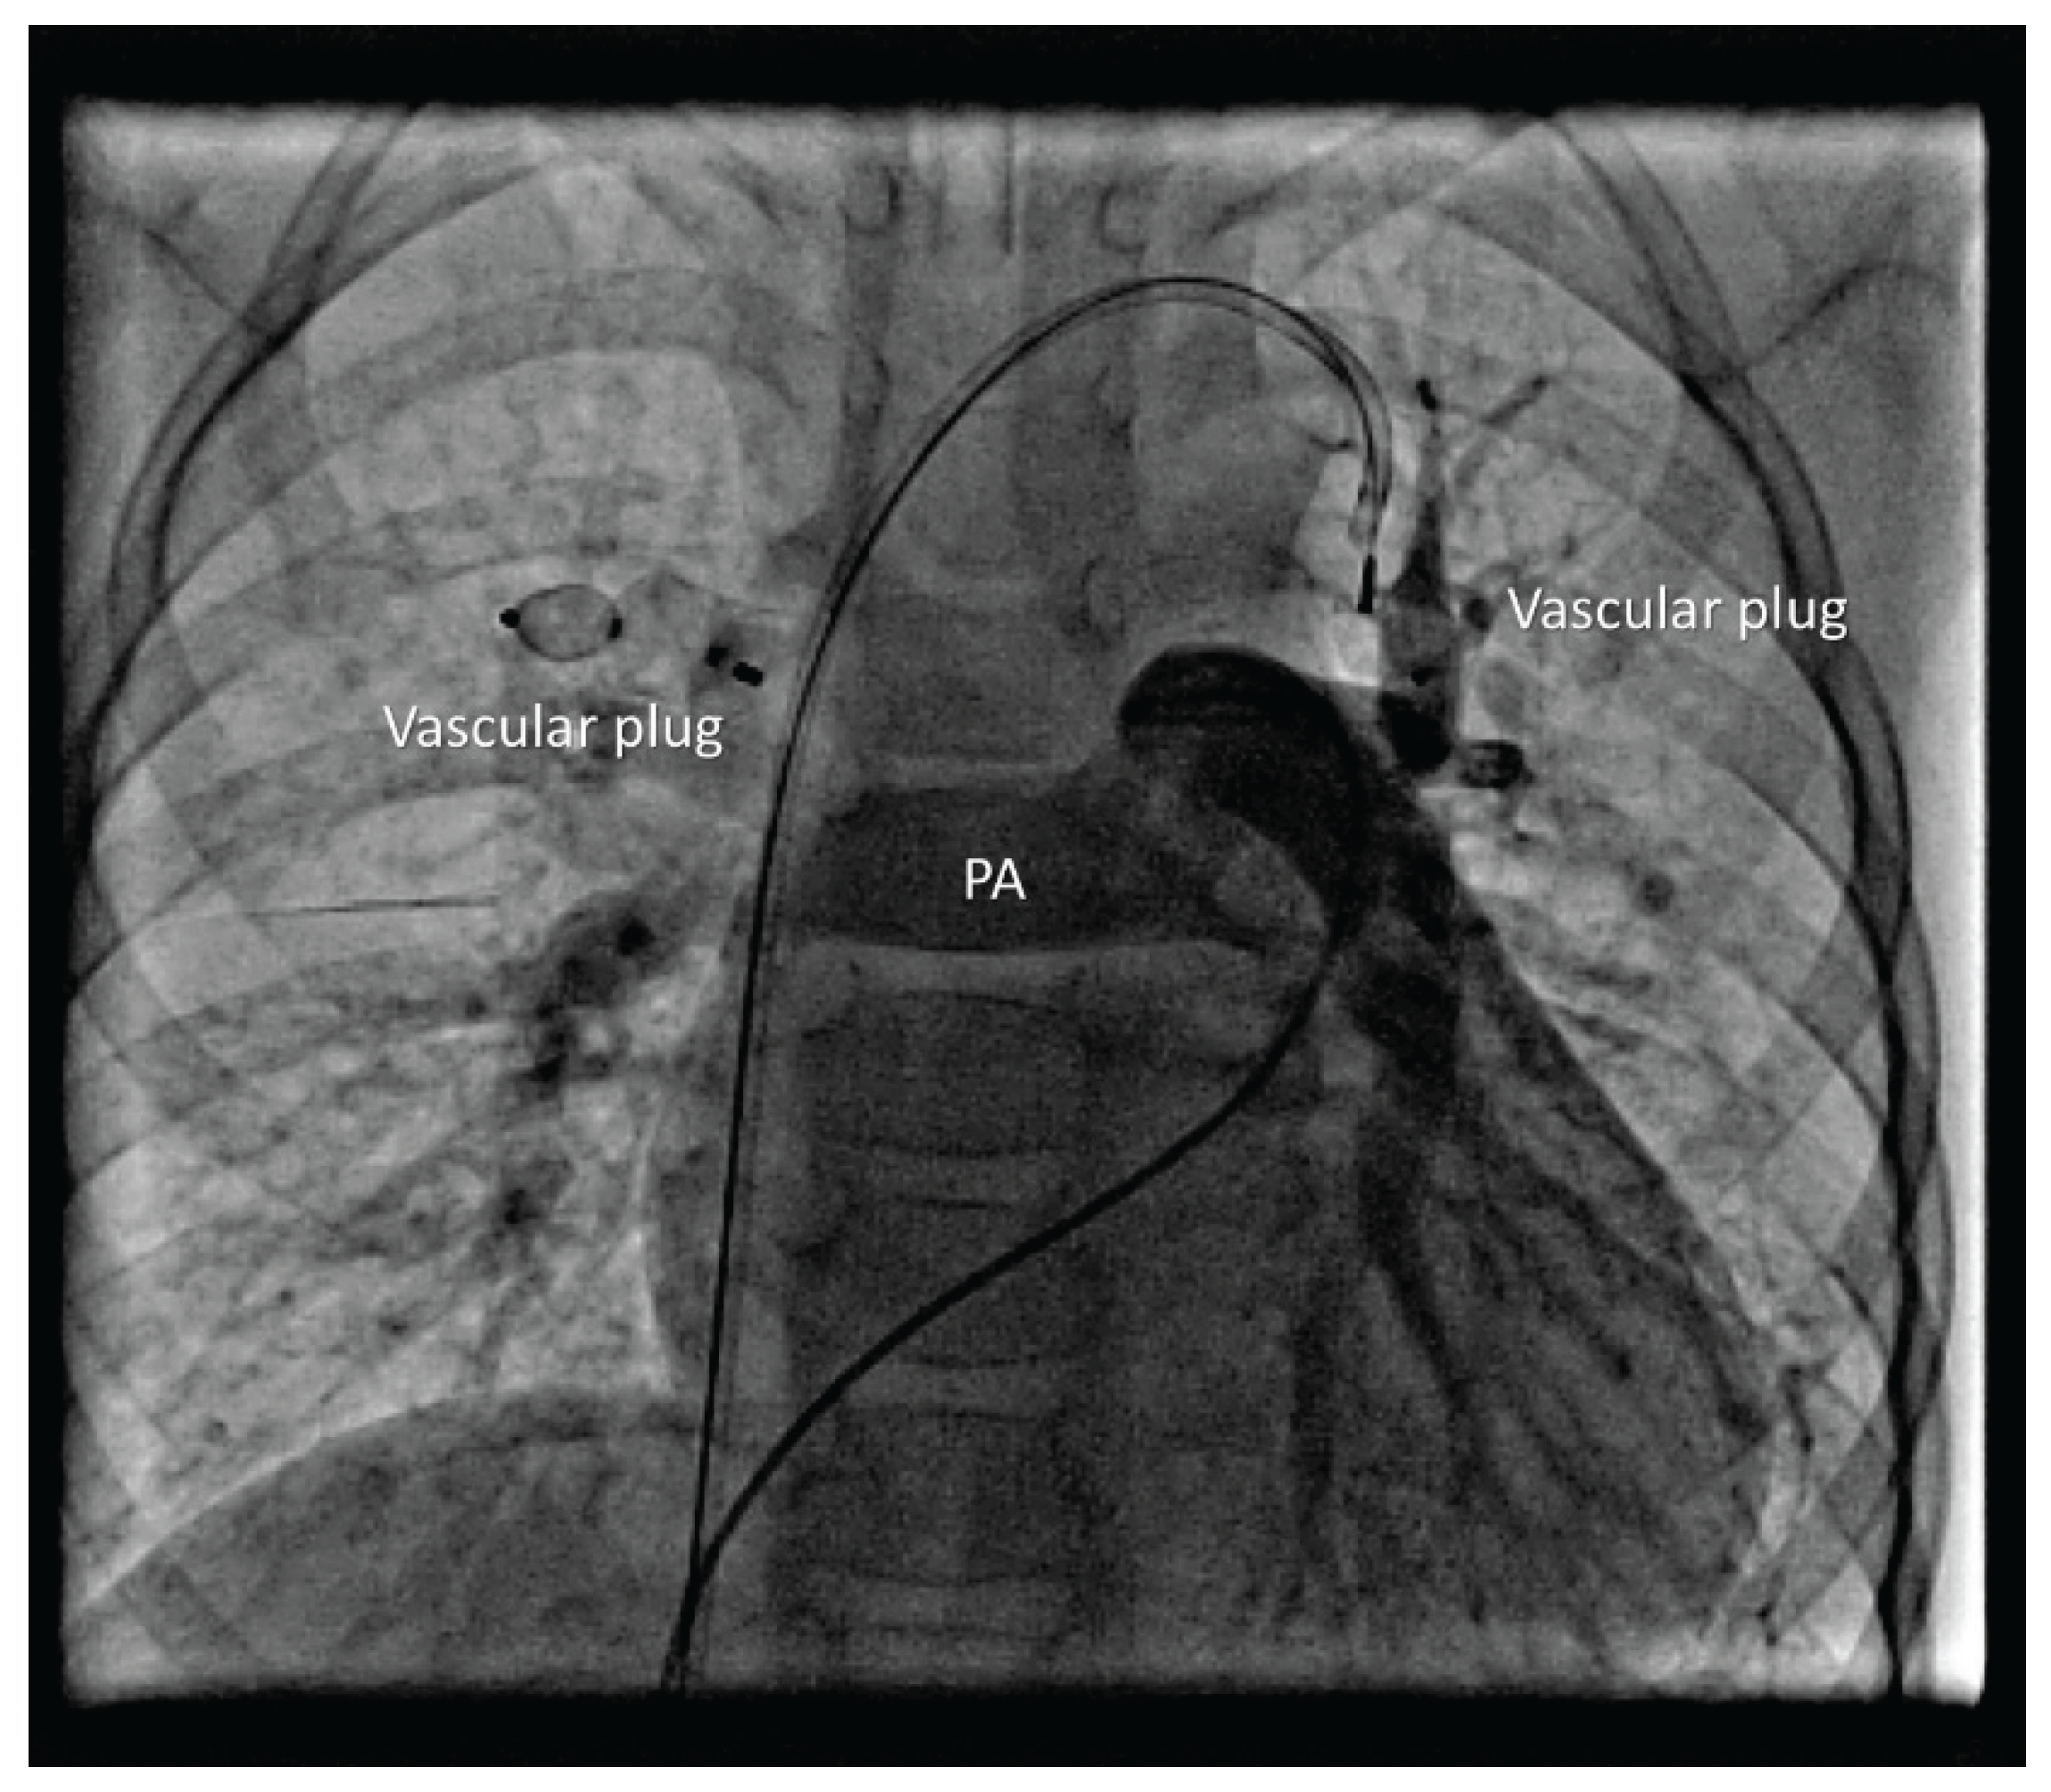

The RLPV drained normally. A 5 Fr sheath was placed in the left femoral vein. Balloon occlusion testing was performed using a 10 × 20 mm balloon in RUPV and LUPV followed by selective left and right PA angiography, respectively (Figure 2). No residual anomalous venous pathways were visualized in either upper pulmonary lobe. Pulmonary venous return drained freely and rapidly into the left atrium, with no significant increase in MPA pressure during prolonged balloon occlusion. A 12 mm Amplatzer Vascular Plug II was deployed in the RUPV (Figure 3).

Device position was verified, and control angiography showed no venous congestion in the right upper lobe before release. A 7 Fr sheath was then placed in the left femoral vein, and a 7 Fr right guiding catheter was advanced into the VV. A 12 mm Amplatzer Vascular Plug I was delivered. After verifying correct position and excluding pulmonary venous congestion, the device was released (Figure 4).

Figure 3. Vascular pluge in RUPV without right upper pulmonary lobe congestion. Anomalous LUPV drains via VV and IV into SVC.